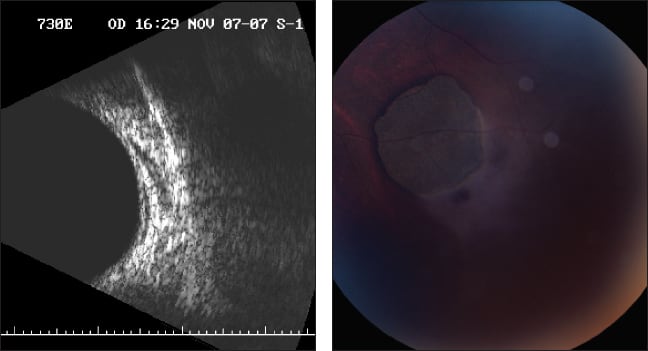

In 2005, two years after this patient's presentation, the lesion appeared to be stable with no noted change (Figures 2 and 3). In 2008, the patient developed lacunae within the lesion (Figure 4). In 2009, slight growth of the lesion and the lacunae were detected (Figure 5). RP

Figures 2 and 3. Two years after the initial presentation, the lesion appears stable.